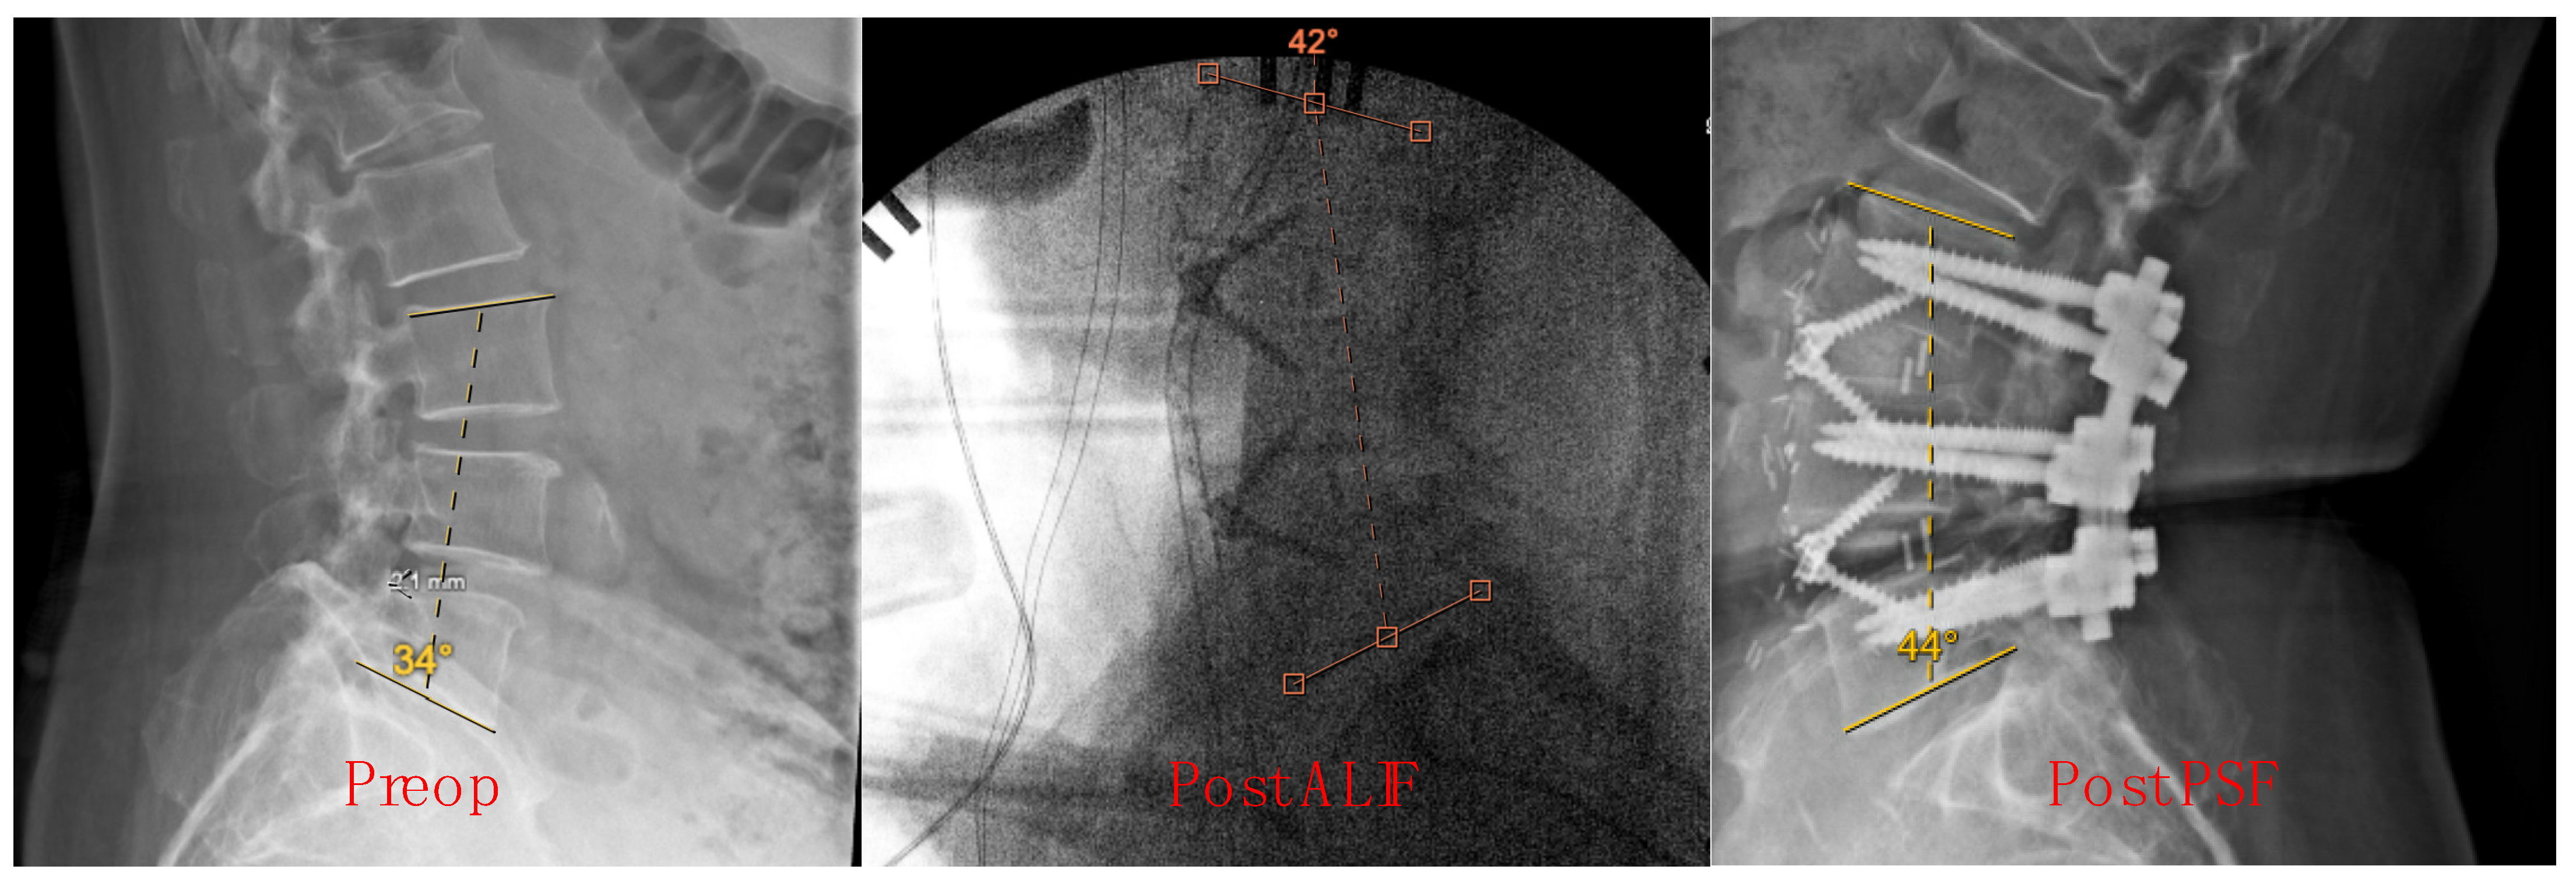

Measurements were conducted at three key time points: before ALIF in the standing position, post-ALIF in the supine position, and post-PSF in the prone position. These specific time points were chosen to capture the dynamic changes in lumbar lordosis throughout the surgical process, from preoperative baseline to immediate postoperative status. The choice of measurement technique was based on its widespread use in clinical practice and its established reliability in assessing spinal alignment [16,17,18]. Additionally, the selected measurement points were consistent with standard protocols for evaluating lumbar lordosis in spinal surgery research [19]. Sample X-ray images illustrating the calculation of preop, post-ALIF, and post-PSF Cobb angles are shown in Figure 1.

Figure 1. Cobb angle measurement at preop, post-ALIF, and post-PSF timepoints.